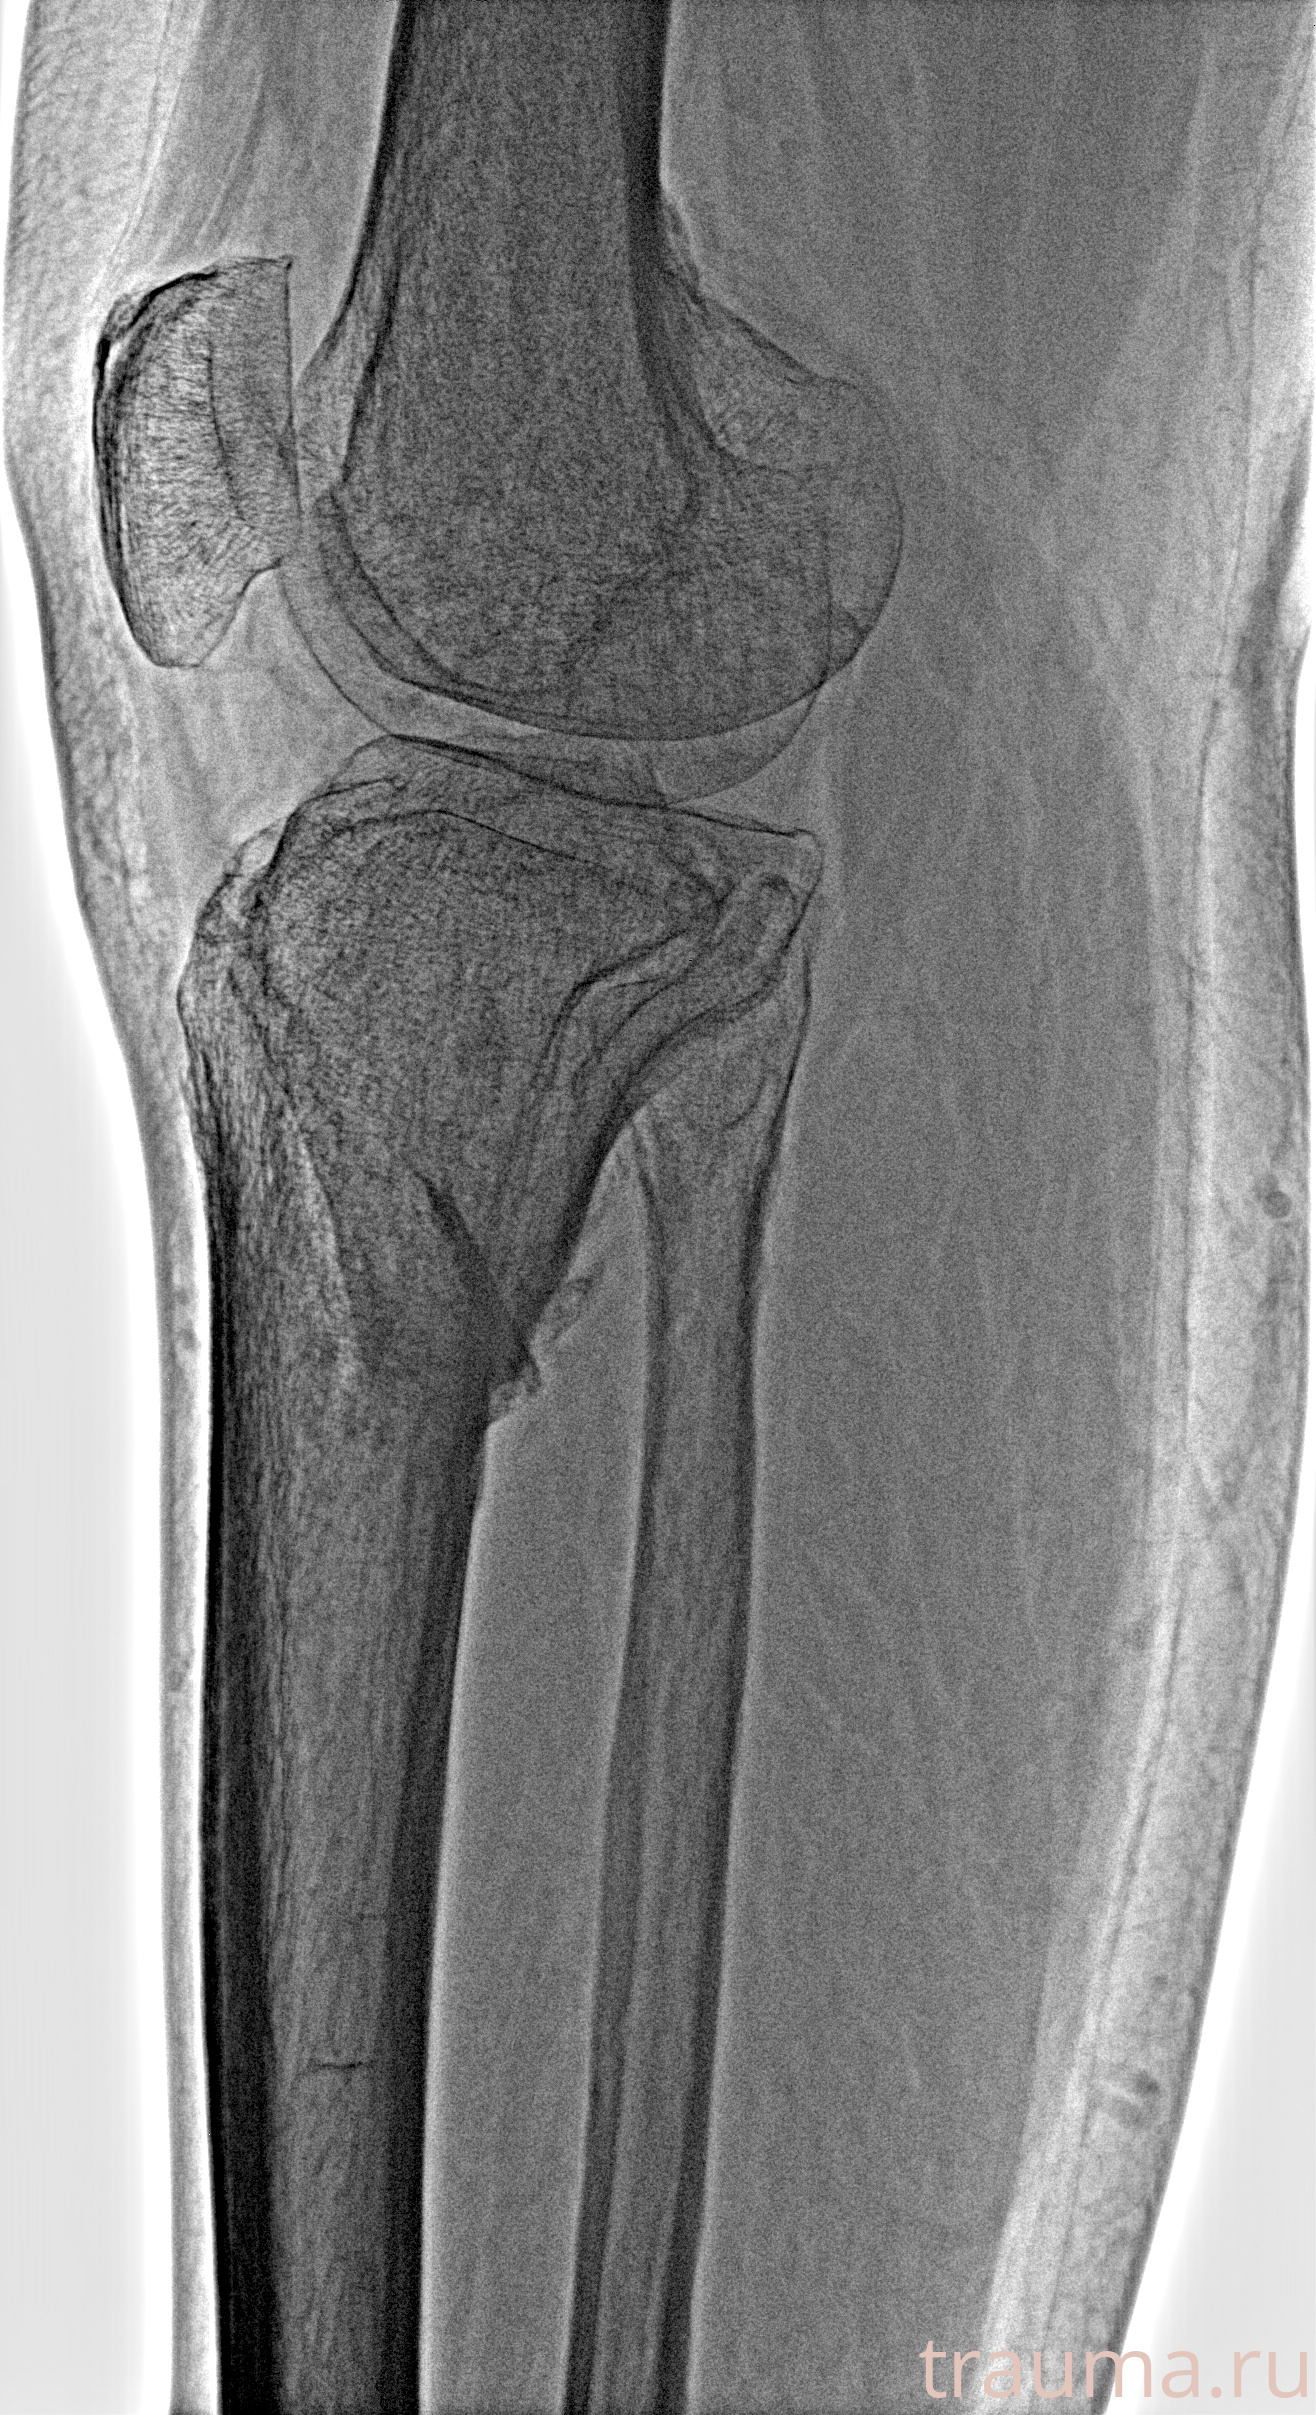

Рентгенограммы

Рентген на дому: по вашему адресу приезжает врач-рентгенолог, травматолог-ортопед с мобильным рентгеновским аппаратом, проводит диагностику травмы или заболевания, делает необходимые рентгенограммы, дает рекомендации по дальнейшему лечению. Получить качественные снимки в домашних условиях возможно благодаря уникальной методике, разработанной МосРентген Центром для института  Склифосовского